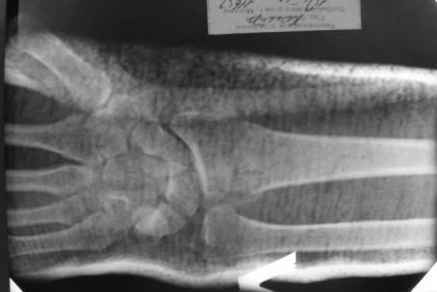

Уважаемые коллеги.Прошу обсудить случай лечения перелома дистального метаэпифиза

лучевой кости. Ситуация скандальная и крайне неблагоприятная.

15.12- перелом луча в Москве. Там же репозиция, гипс. Дальнейшее

лечение у нас в ЦРБ. 20.12.- вторичное смещение в гипсе

21.12- под внутривенным наркозом - репозиция, гипсовая лонгета.

Объективно говоря- снижена высота лучевой кости, диастаз лучелоктевого сочленения, и не

сросся шиловидный отросток. однако на РКТ при сравнении с другой стороной- разница

незначительная.

1.Прошу объективно оценить качество нашей репозиции на момент 21.12. (неужели так плохо?).

Что на снимках при снятии гипса- сам вижу.

2. сравнить снимки РКТ (с двух сторон)- так ли велико укорочение лучевой

кости и лучелоктевой диастаз.